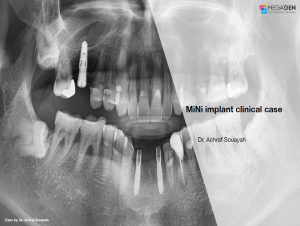

Aesthetic zone,AnyRidge,Clinical case,Dr. Achraf Souayah,Edentulous,Guided surgery,Immediate Placement,Mandibular Anterior,Mandibular Posterior,Maxillary Anterior,Maxillary Posterior,MEG-Rhein,MILA Kit,Overdenture system,Sinus Elevation